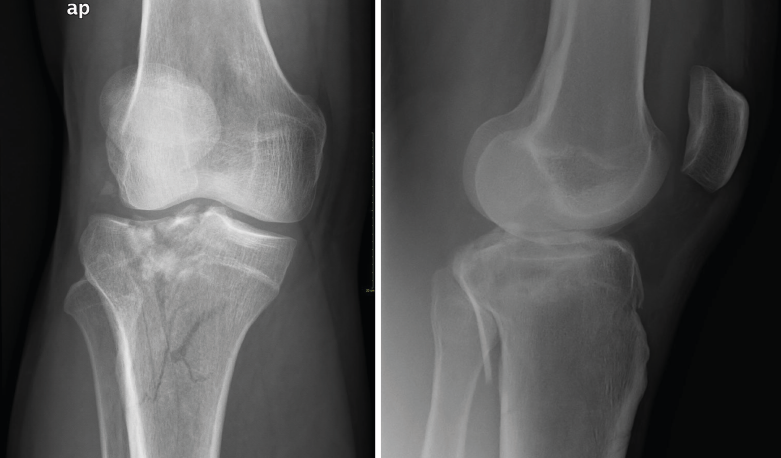

1.1.2. Tibia (Figura 2)

Figura 2. Radiografías anteroposterior y lateral de rodilla: fractura con varios trazos de meseta tibial externa.